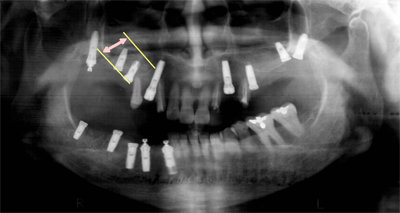

インプラントを埋入します。

インプラント先端部分の骨が足りず、飛び出している状態がわかります。

開けた穴より、自家骨(骨を削った際に出たものや、骨の充分ある別の部位より集めたもの)を填入する膜を押し上げながら、インプラントを埋入します。

充分な骨が充填された状態になれば、開けた穴を特殊な膜で塞ぎ、歯肉を縫合していきます。